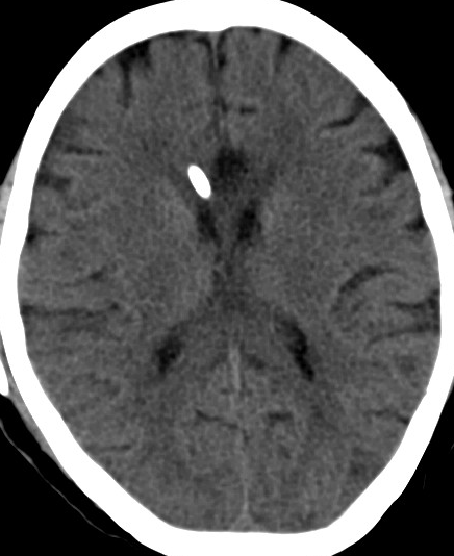

2014-11-28 CT

2015-12-13 MRI

2015-1-30 DSA

2015-2-1

在局麻下行腰椎穿刺术+ 测脑压术,患者取左侧卧位,测量脑脊液压力为60mm水柱。

脑积水 OR 颅内静脉血栓?

低颅压原因?(分流泵故障?脑顺应性差?)

头痛面部麻木的原因?(三叉神经痛?)

2013-5-16 MRI

2013-8-2 CT

腰穿脑压240

2014-10-17 CT

仍时有前额部疼痛,程度轻,调压190—200

脑压为60mm水柱